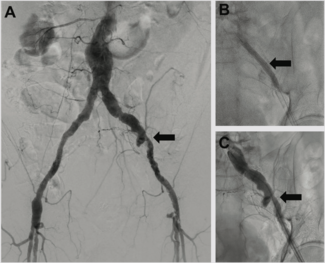

With the use of IVL, we are now at a point where the only cases that we have to either transfer or stage are non-crossable lesions: cases where you can get a wire but not a balloon across, and these are fairly rare.